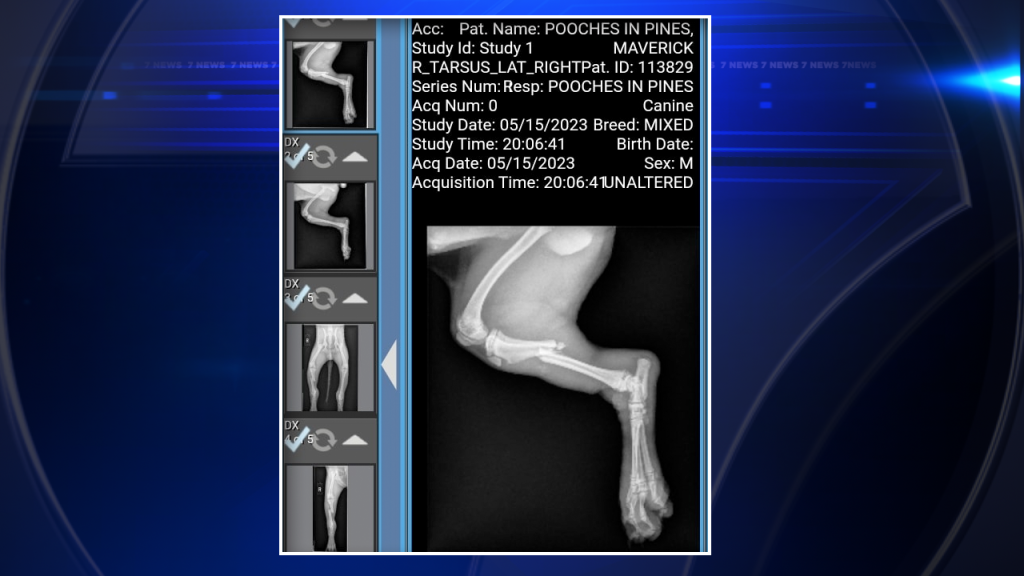

Following a series of tests, it was revealed that Maverick sustained a tibia fracture and a fibula fracture. Additionally, the young canine was found to have multiple infected wounds and lacerations across his body.

Maverick was put on a cocktail of medications, received IV fluids, and had a catheter inserted. As much as they wanted to save his left hind leg, the risk of infection spreading was too high.

In addition to the fractures, his legs had deep wounds that were badly infected, with necrotic tissue. Surgery to repair the fractures would increase the chances of infection and make his recovery even more challenging.

“We were going to try to do plates and pins for his leg, but because of his infections and stuff that he has, due to his young age, the vet decided that it would be best to amputate his leg,” said Goodwin.